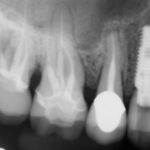

Charles P.

This patient had an Implant placed to replace a missing molar which had been removed due to infection.